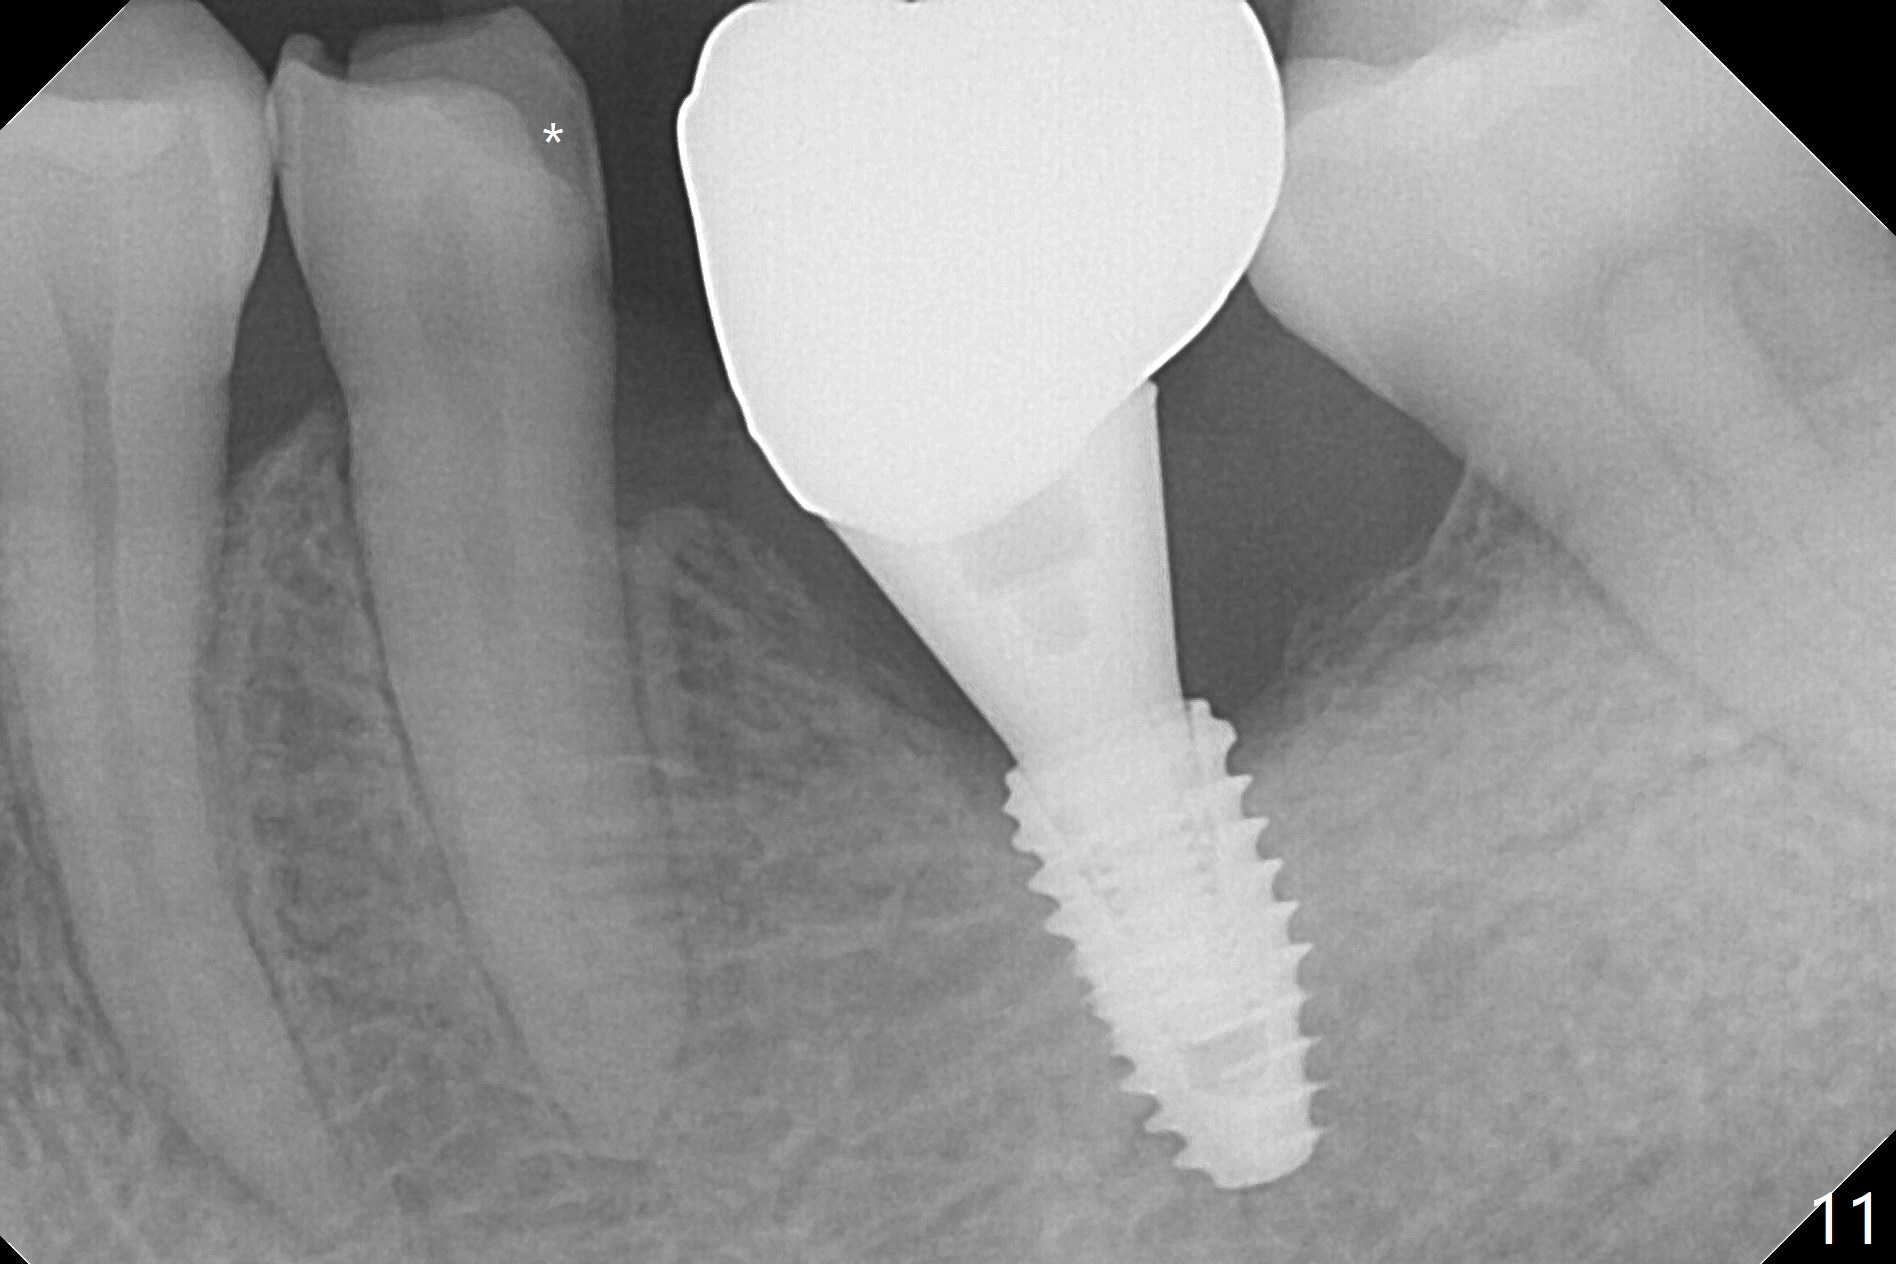

With 34 mg of Lidocaine and 17 mcg of Epinephrine (local infiltration), a 4.5x8.5 mm implant is placed with guide. The insertion torque is ~50 Ncm. It is placed in precise depth and in a short period of time (tolerable to the operators and patient, easier than mini-implant placement, Fig.1). There is no postop pain or paresthesia. The mesidistal position is within treatment plan (Fig.2). Miniimplants are placed to intrude #14 14 days prior. The teeth #16,17 and 32 are extracted 3 months postop. Minimal bone resorption at the crest is noted nearly 4 months postop (Fig.3). Bands and brackets are placed #18 upright 4 months postop (Fig.4 (14 niti wire)). The buccal and lingual view of the preop model shows that the supraerupted 1st molar (#14) has close relationship with the distal surface of the tooth #20 (Fig.5,6), accounting for the severe wear of the latter (Fig.8-11). The implant not only acts as an anchor to upright #18 in 4.5 months post banding (Fig.7 *), but also as an occlusal stop so that #18 has no interference to be moved. The stress on the implant results in radiating trabecular pattern (Fig.7,11 (9,11 months postop), as compared to before loading (Fig.1,3)). Restoring the distal contour of #20 with composite (Fig.12 C) makes it easy to close the space by adding porcelain the mesial surface of the implant crown. The crown/abutment is loose in China 7 months post cementation.